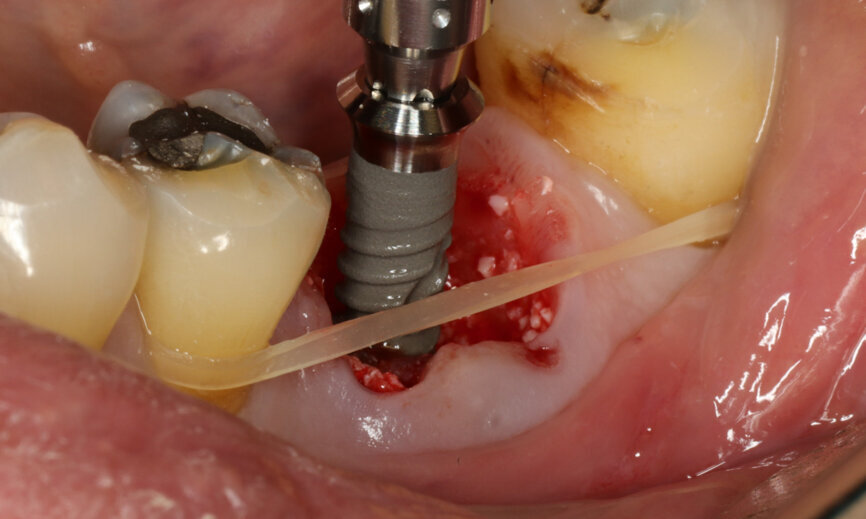

Fig. 13: Straumann TLX implant insertion.

Fig. 14: Implant in final position with bone augmentation.

It was possible to verify solid interradicular bone availability (Fig. 5), extending further the limits of the root apices and allowing for a centrally oriented osteotomy. The implant bed preparation started with the use of a needle drill at 800 rpm, followed by the ⌀ 2.2 mm and ⌀ 2.8 mm drills (Figs. 6–10). The implant was placed with the use of ratchet and torque control, reaching the desired final position at a 50 N cm torque value (Figs. 11–13). The socket was then augmented with bovine-derived bone substitute impregnated with advanced platelet-rich fibrin (A-PRF) and finalised with sutures to keep the A-PRF application immobile, and a 3 mm healing abutment was placed (Figs. 14–17).